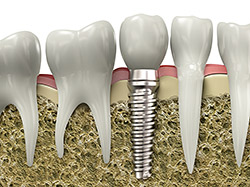

Dental implants are advanced dental solutions designed to replace missing teeth. They consist of a titanium post that is surgically placed into the jawbone, acting as a sturdy foundation for artificial teeth or crowns.

This innovative approach mimics the natural tooth root, providing stability and support for restorations that look, feel, and function like real teeth.